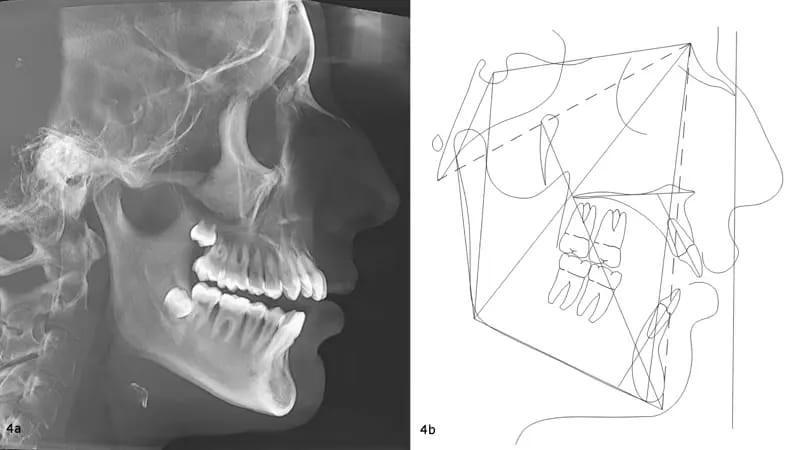

Панорамная рентгенограмма подтвердила наличие всех четырех зачатков третьих моляров. Примечательно, что в верхней челюсти наблюдалась выраженная резорбция корней, хотя общее состояние пародонта казалось хорошим (фото 3). Цефалометрический анализ показал тип скелета II класса, тенденцию к вертикальному росту и заднюю ротацию нижней челюсти. Было обнаружено, что резцы верхней и нижней челюсти слегка наклонены (фото 4).

Фото 4a-b: Дооперационная цефалометрическая рентгенография перед лечением (а) и трассировка (b).